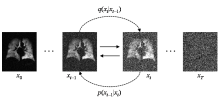

ZHANG Mingyu, XIAO Sa, SHI Shengjie, ZHANG Xuecheng, ZHOU Xin. Research on a Multi-modal Enhanced Denoising Diffusion Model for Hyperpolarized 129Xe MRI[J]. Chinese Journal of Magnetic Resonance, 2025, 42(4): 364-377.